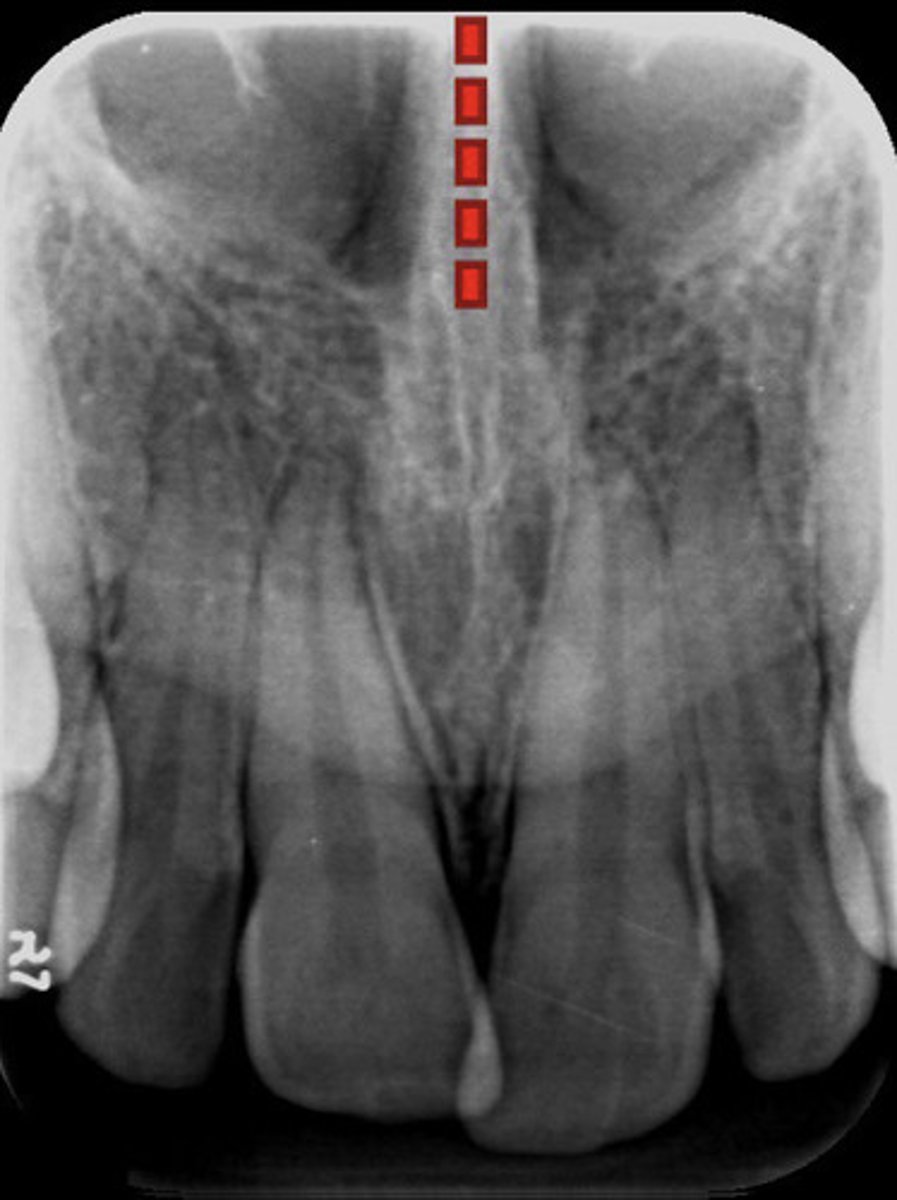

Intermaxillary suture

What is the red dotted line representing?